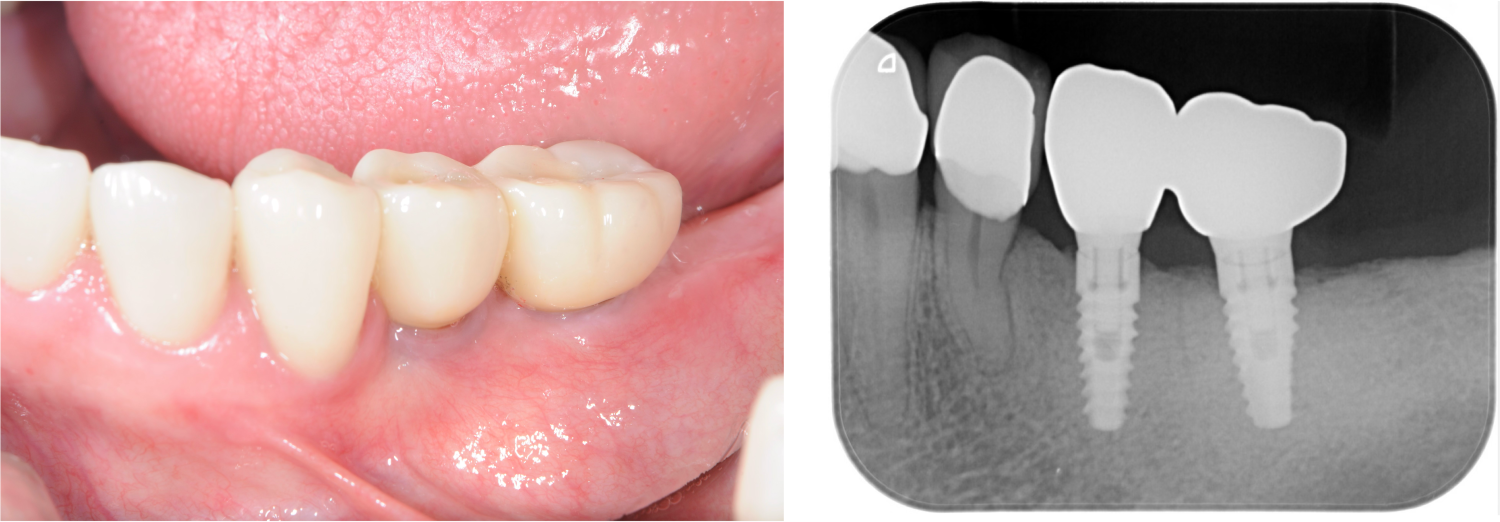

少数歯欠損のインプラント治療の症例(うえだ歯科)

| 主訴 | 全顎治療希望、右下の歯が動いて痛いので噛みずらい。当院でインプラント治療したお母様からの紹介 |

| 治療内容 | プラークコントロール不良なため歯周治療を行い、保存不能の歯を抜歯し、抜歯窩の治癒を待って、欠損部にインプラントを施し咬合再構成を行う。 プロビジョナルレストレーションによる咬合関係を模索した後、全顎にわたりセラミックによる補綴治療、その後メインテナンスに移行 |